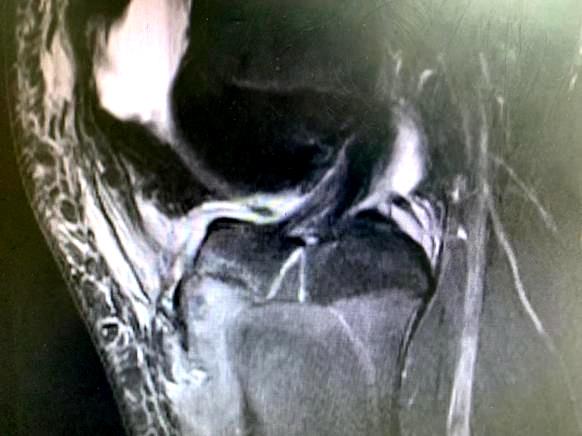

患者脛骨結(jié)節(jié)撕脫骨折影像

這次收治的患者屬于Ogden 3A型,手術(shù)指征明確,手術(shù)團隊采用骨折端切開復位空心釘內(nèi)固定+髕韌帶可吸收錨釘重建術(shù)+經(jīng)膝關(guān)節(jié)鏡探查、清理的手術(shù)方式,獲得滿意效果。